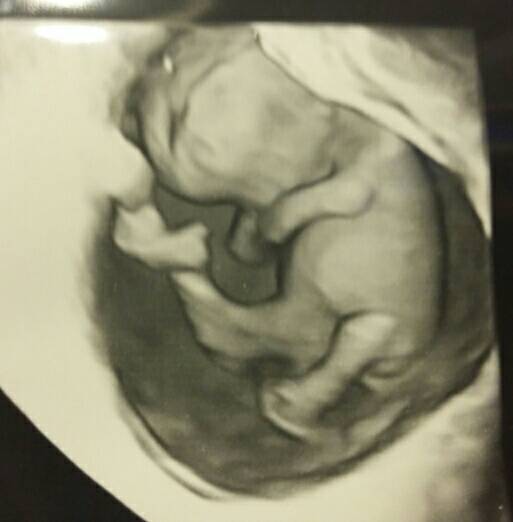

11 tydzien powinien być skończony chyba. Ja miałam taką samą sytuację miałam iść w piątek w 11t5d ale ze ciąża kilka dni młodsza lekarz na SORze doradzil mi przesunąć i moja dr prowadząca ciążę się z tym zgodziła i przesunela na 12t1d ale ostatecznie idę 12t3d bo mąż wtedy może że mną jechać.Bo ja mam wizyte teraz w srode,wg OM bedzie to 11t5dni,a ze dzidzia okolo tydzoen mlodsza to bedzie gdzies tak 10t5d czyli 11 tydzien jak sie liczy...to w srode byloby to usg robione z tym mierzeniem kosci nosowej i przeziernosci czy to jeszcze za wczesnie? Jak myslicie?